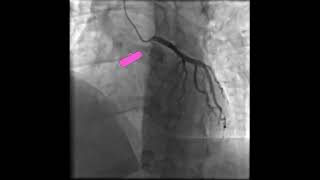

RAO Caudal View of LCA | LM, LAD & LCx Bifurcation | Cineangiography

Cineangiography